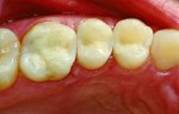

Antes![]() |

Depois![]() |

Vantagens das restaurações estéticas:

- Simples e rápidas (na maioria numa só consulta)

- Baixo custo

- Qualidade estética excelentes